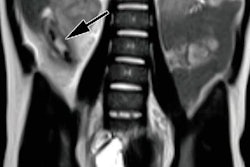

Interestingly, more female pediatric patients underwent neurological MRI scans than their male counterparts, with a ratio of 1.4 to 1. One possible explanation is that girls presented with a higher rate of headaches. The researchers also found that ED clinicians used fast spine T2 imaging sequences to rule out hydrocephalus.